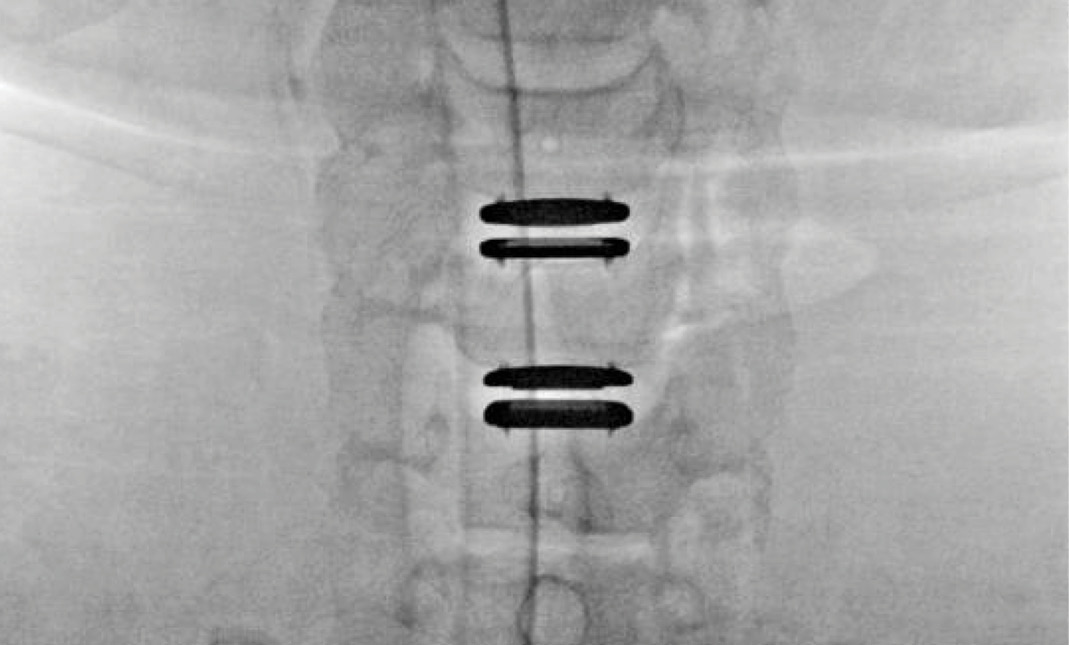

During the procedure, prodisc C Vivo fit well within the C4-5 concave endplate. I expected to use a flat endplate prodisc C SK at C5-6, however I trialed the domed prodisc C Vivo and it actually looked good, so I unexpectedly used matching implants.

It was very helpful to have the flexibility to use either a flat or a domed implant at either level. Having the different size options available to truly match patient anatomy that the Match-the-Disc™ System provides enabled me to avoid having to alter the patient’s anatomy to fit the device.